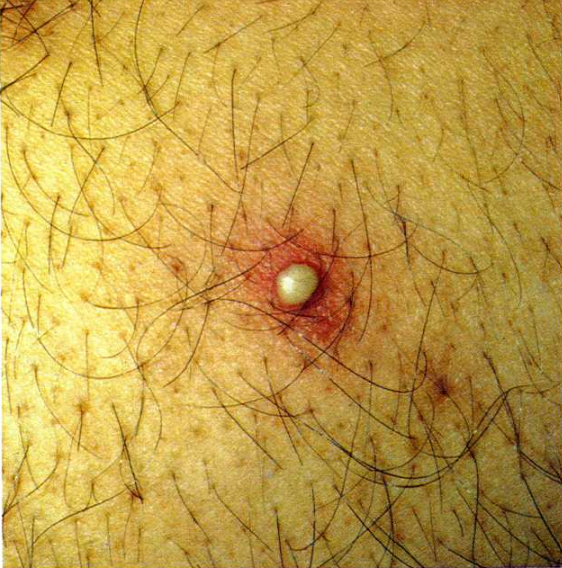

ENFEKTE YARA

Enfekte yaralar, mikroorganizma bulaşma olasılığı yüksek olan yaralardır.

Enfeksiyon oluşma riski yüksek yaralar şunlardır:

-Üzerinden 6 saat geçmiş yani gecikmiş yaralar,

– Kenarları düzgün olmayan yaralar,

-Cerrahi dikişleri ayrılmış yaralar,

-Çok kirli ve derin dokuların (damar, kas, sinir vb.) hasar gördüğü yaralar,

-Ateşli silahlarla meydana gelen yaralar,

-Böcek, yılan, köpek gibi canlıların ısırma ve sokmaları ile oluşan yaralardır.

Enfekte yaralar, mikroorganizma bulaşma olasılığı yüksek olan yaralardır.

Enfeksiyon oluşma riski yüksek yaralar şunlardır:

-Üzerinden 6 saat geçmiş yani gecikmiş yaralar,

– Kenarları düzgün olmayan yaralar,

-Cerrahi dikişleri ayrılmış yaralar,

-Çok kirli ve derin dokuların (damar, kas, sinir vb.) hasar gördüğü yaralar,

-Ateşli silahlarla meydana gelen yaralar,

-Böcek, yılan, köpek gibi canlıların ısırma ve sokmaları ile oluşan yaralardır. -